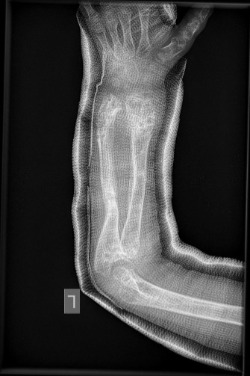

Η εικόνα απεικονίζει περιστατικό με παρουσία γάγγλιου, όπου πραγματοποιήθηκε αφαίρεση του απο τον Δρ. Ζένιο.